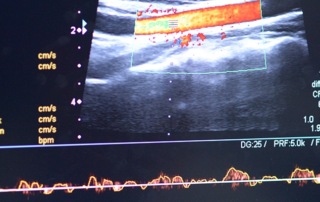

Ultrasound Use for Vascular Access and Basic Cardiac and Pulmonary Assessment for Nurses

Daniel Nash, CRNA, DNAP reviews how nurses can use ultrasound for vascular access and basic cardiac and pulmonary assessments.